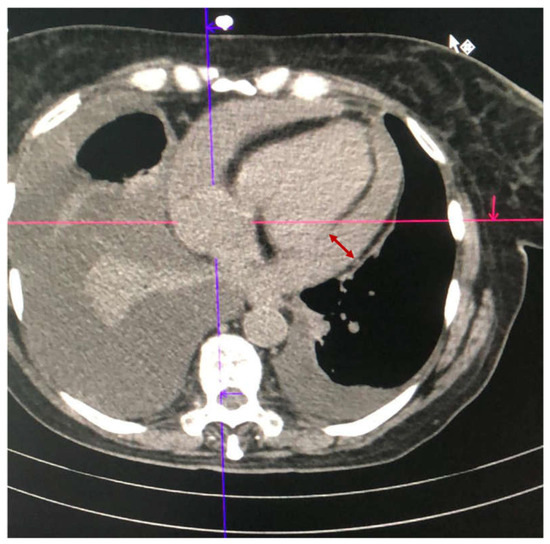

2.1. Case 1

2.2. Case 2

2.3. Case 3

2.4. Case 4